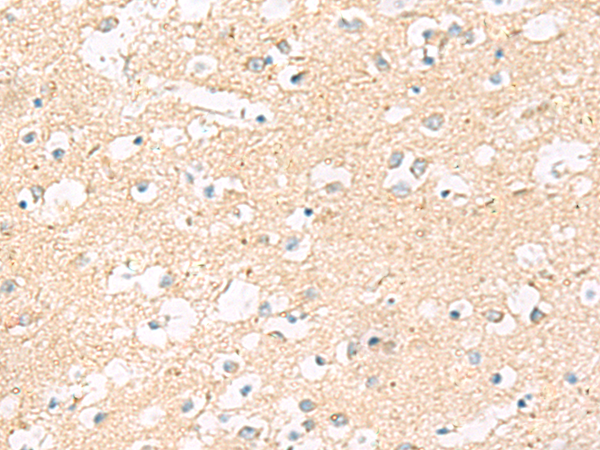

分类: 科研抗体货号: P09813别名: 39K2; 39K3应用: IHC反应种属: Human, Mouse, Rat